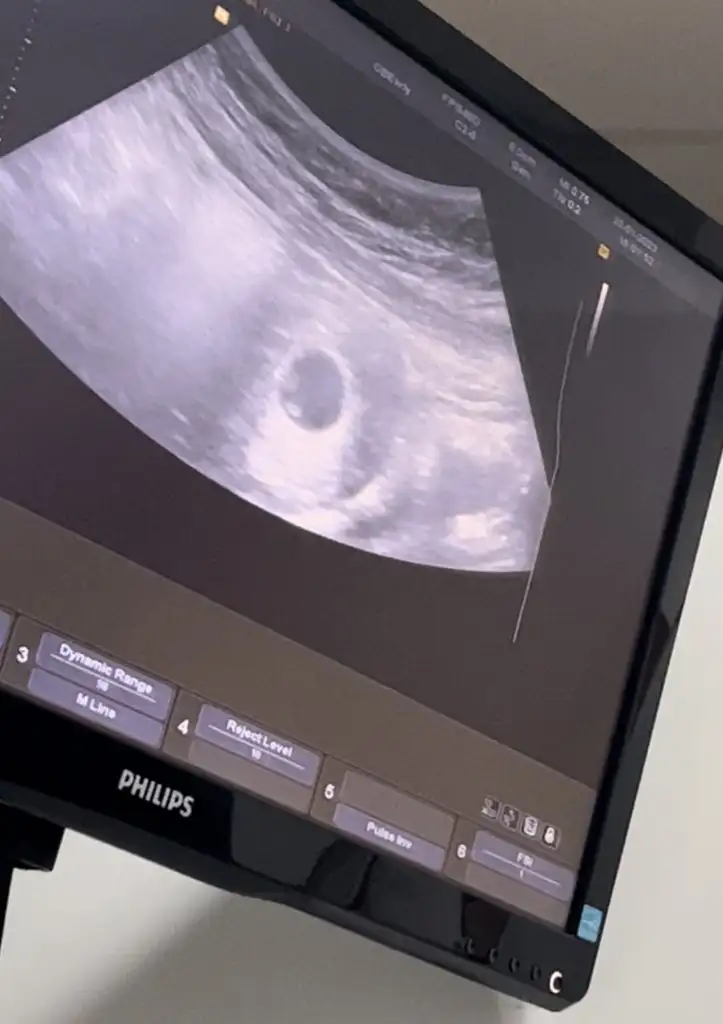

Karından canım ama ikizlik şüphesi var sence ikiz de olabilir mi yoksa birisi yolk kesesimi doktorum net birşey söylemedi🥰❤️

Canım plasentanın parlak tarafı assa doğru duruyor asla anlamadım bebegn konumuna göre plasentanın sola daha yakın oldgnu düşünürsek erkek dye tahmin yuruteblrm canim.

Bu arada ikiz gibi evet gerçekten :)

Cidden ikiz mi dersin ama tek kalp atışı vardı doktor da pek emin olamadı yolk kesesi olabilir dedi bende hayatımda ilk gördüğüm ultrason görüntüsü olduğu için hiç bi bilgim yok günlerdir deliricem yani🫣🥹hormonlarım zaten tavan tek gebelikte böyle olmuyor mu özelden daha netlerini atsam sana bakabilirmisin🙈🥹🥹🥹❤️🙏